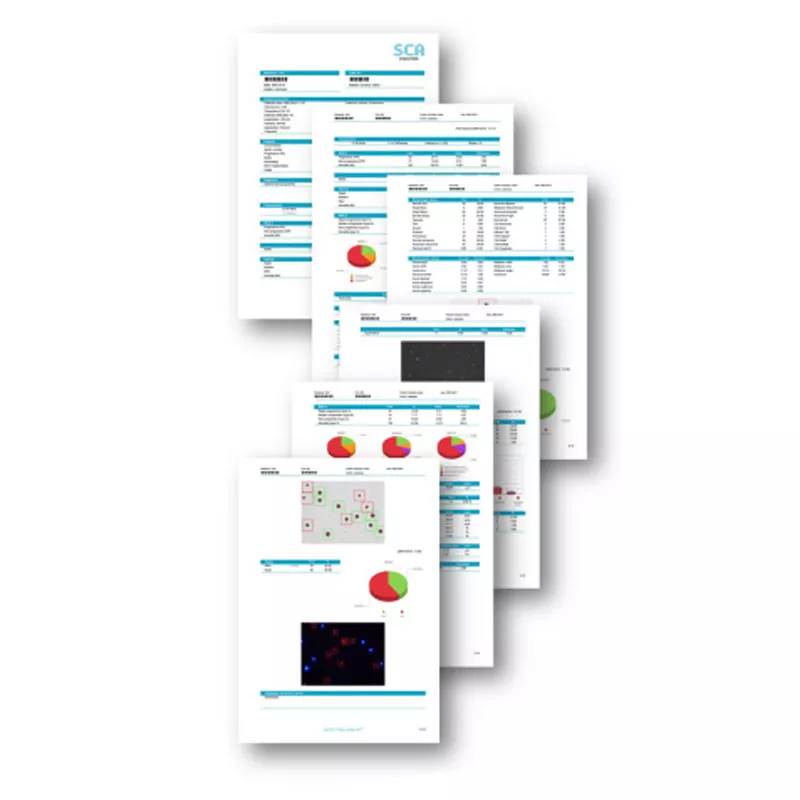

SCA® Customized reports